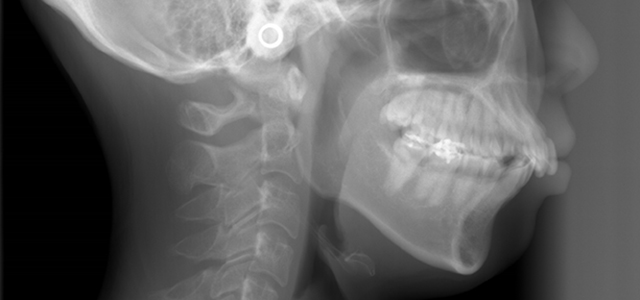

矯正前 側面セファロ

矯正後 側面セファロ